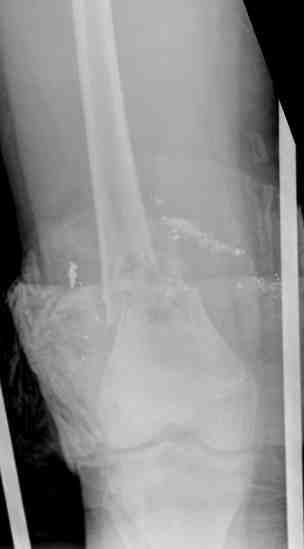

Выше приведены рентгенограммы 13-летнего подростка, страдающего от огнестрельного многооскольчатого перелома дистальной трети бедра. AO наружный фиксатор наложенный в день травмы не дал приемлемой редукции. Через три недели после перелома аппарат Илизарова был наложен без попытки одномоментной репозиции на операционном столе. There are X-Rays of a thirteen year old boy with a comminuted distal femur fracture secondary to a gunshot wound, initially treated with an AO external fixator. The alignment was unacceptable and an Ilizarov external fixator was applied three weeks after the injury. No attempt of definitive reduction was made during the surgery.

Гексаподная приставки наложена на 10 дней и приемлемая редукция была получена. The Hexapod set was applied for ten days and acceptable reduction was received.

По окончанию редукции Гексаподный сет был снят и дальнейшее ведение больного проходило в стандартном режиме аппарата Илизарова. Хороший анатомо-функциональный результат был получен. When reduction was finished, the Hexapod set was removed and further management has been continued by standard Ilizarov regime. Good anatomic and functional results were achieved.